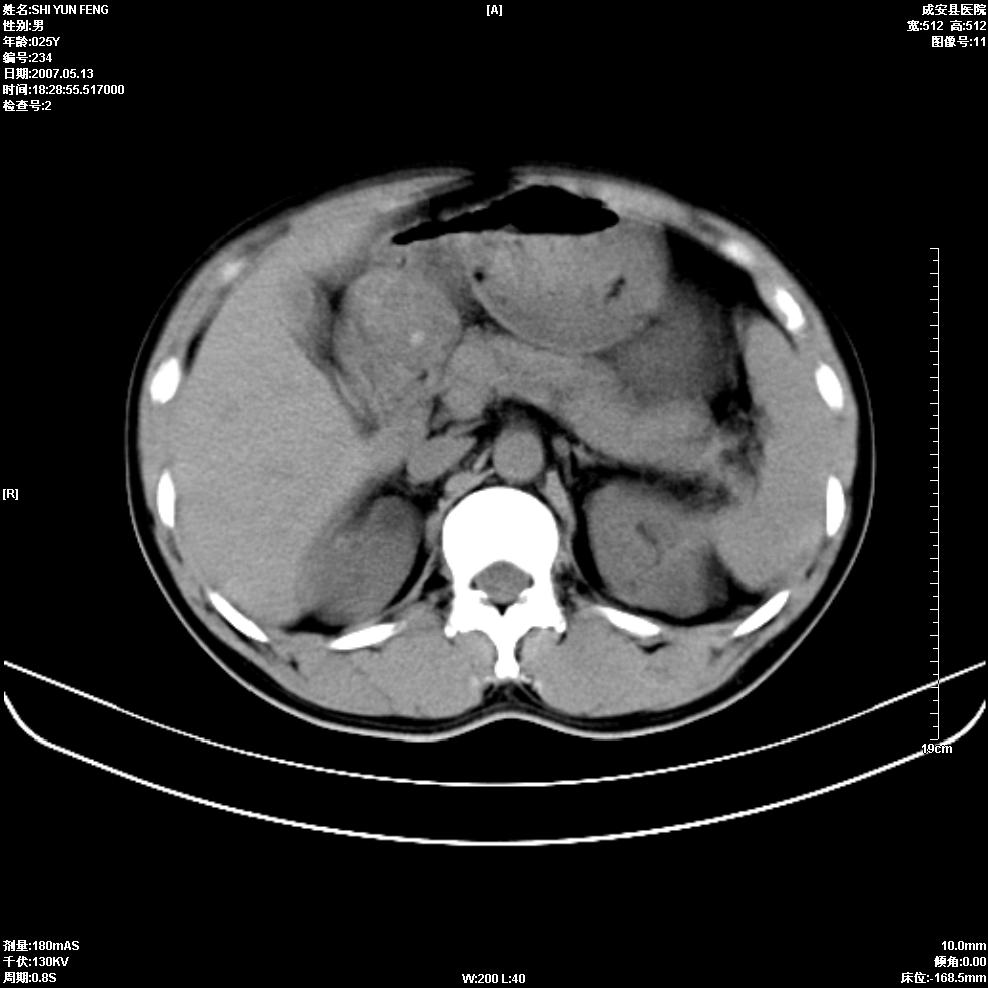

以下是引用zhangzhongshou在2007-5-16 7:36:00的发言:[br]多发性肾囊肿,左肾多发结石。不是多囊肾,楼主箭头所指多考虑左肾囊肿内结石或钙乳,髓质海绵肾不完全除外。[br][br][本贴已被 zhangzhongshou 于 2007-5-16 7:37:18 修改过][br][br][本贴已被 zhangzhongshou 于 2007-5-16 18:15:09 修改过]